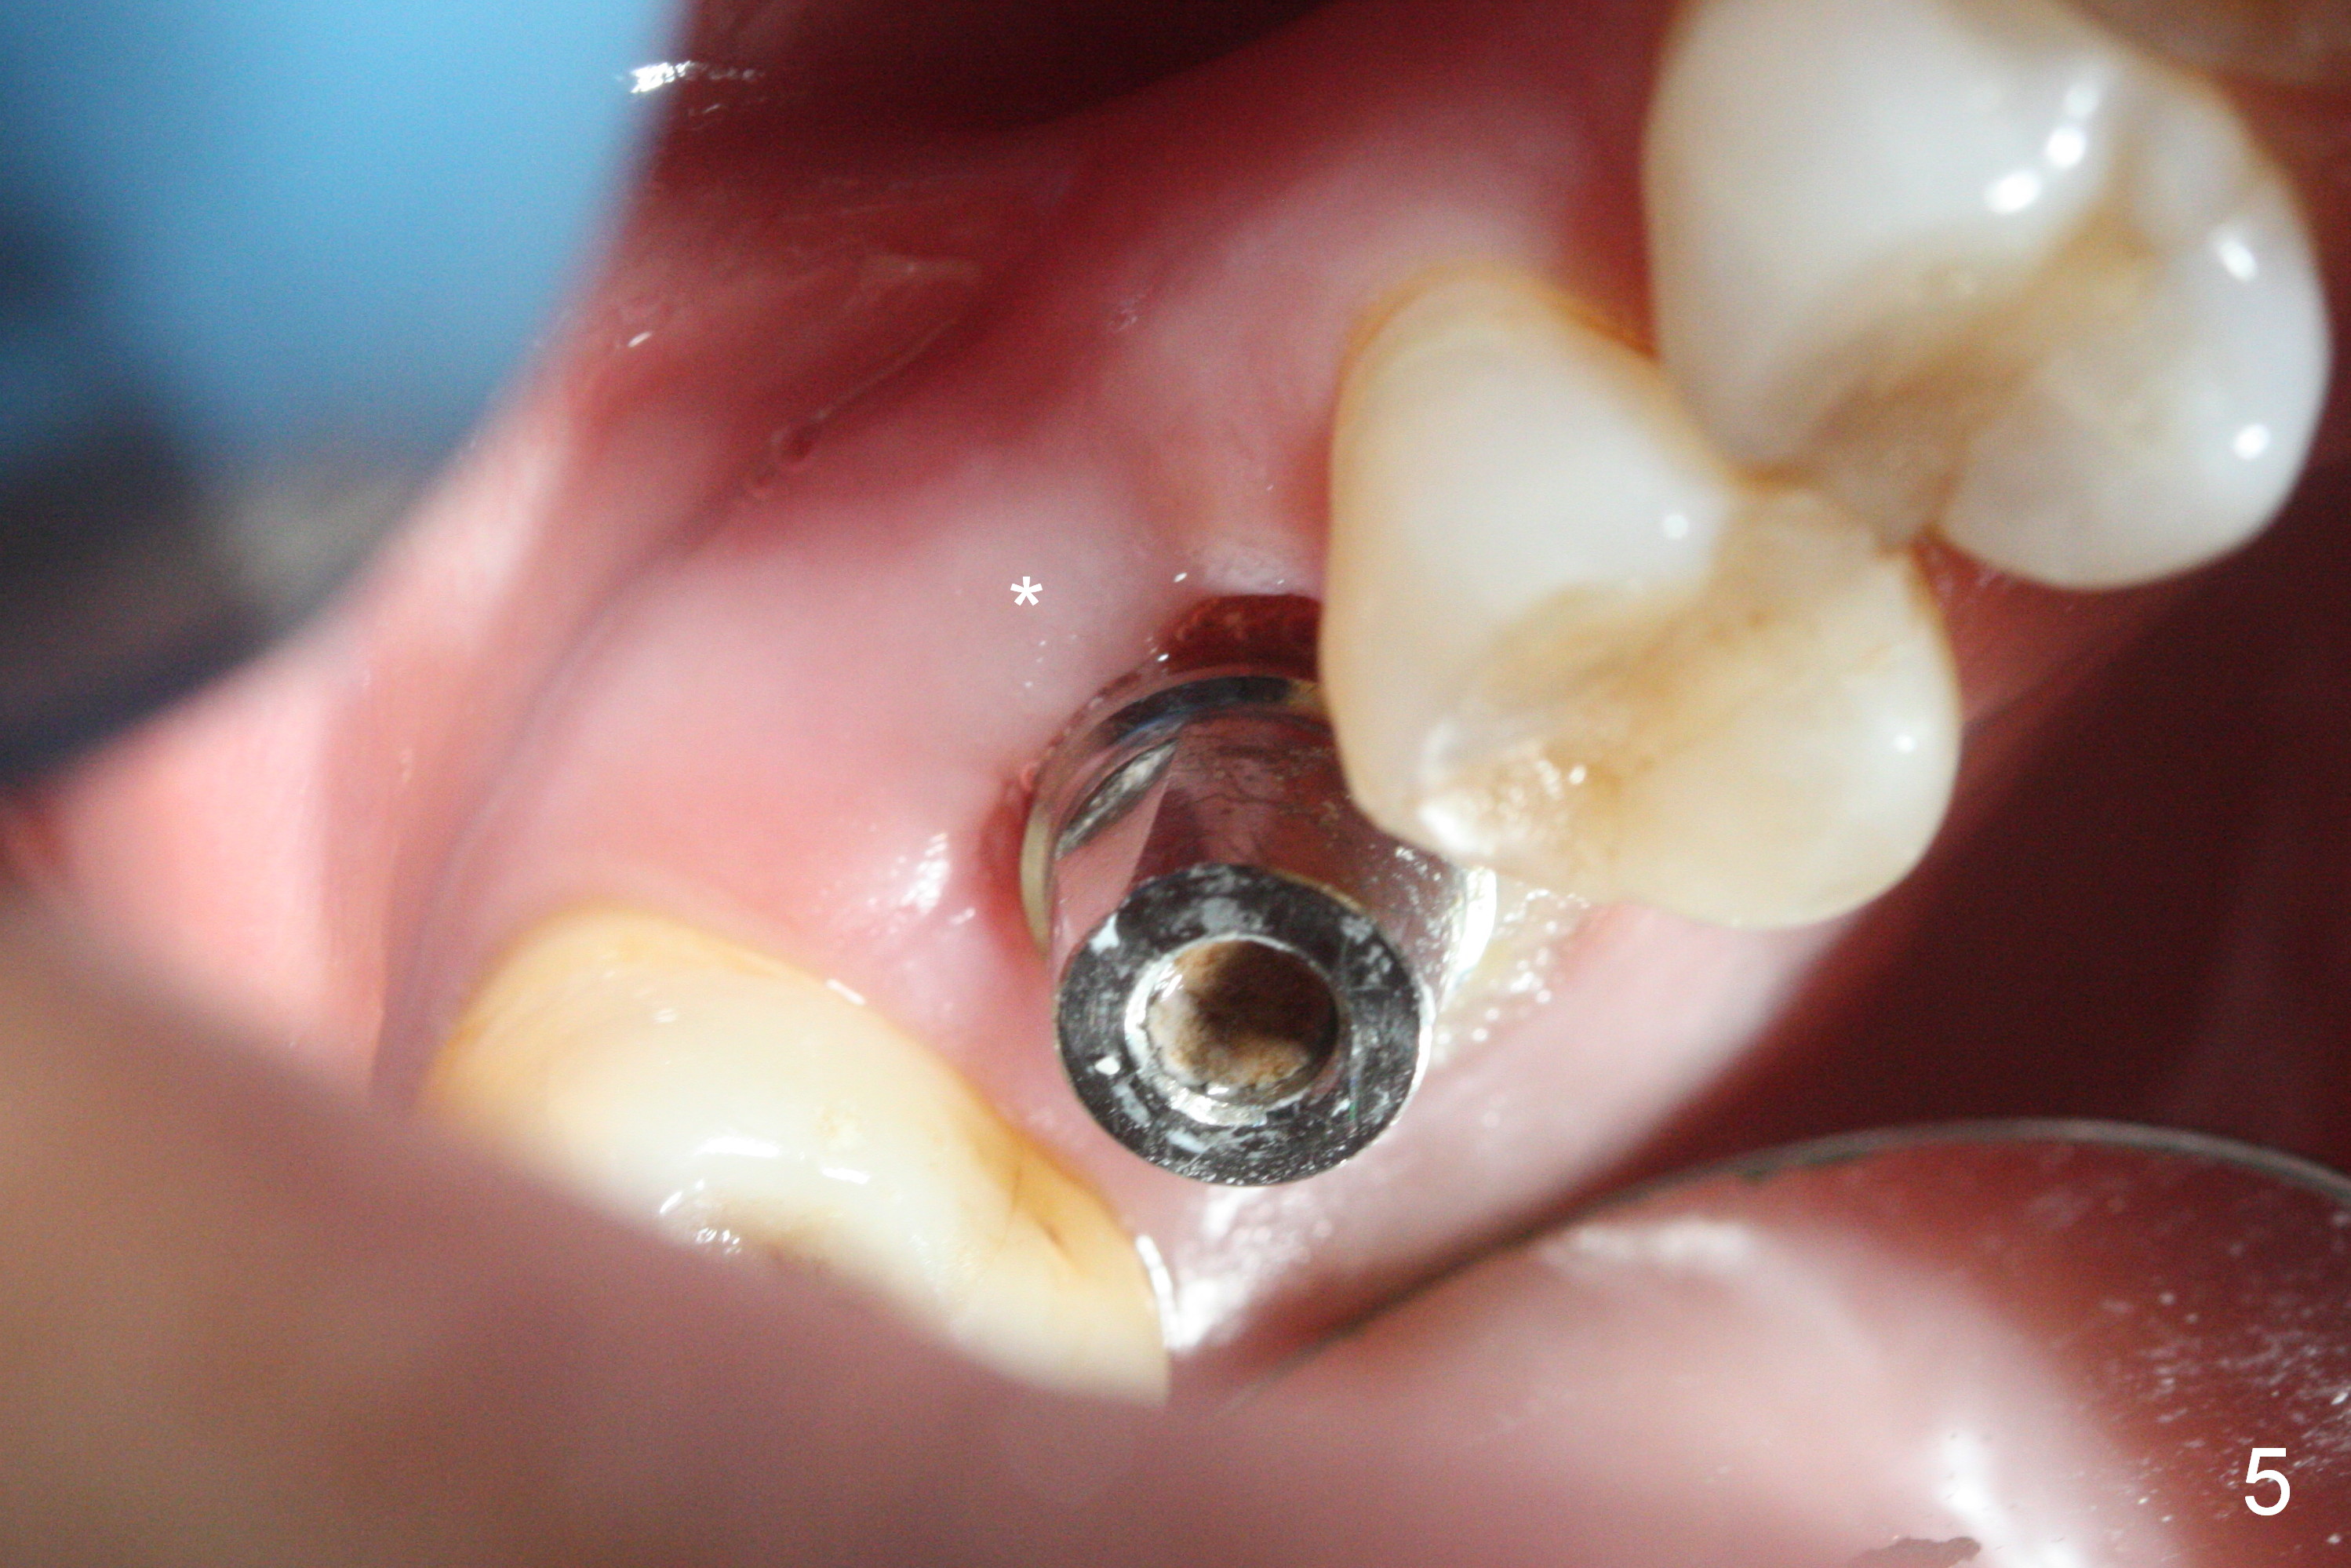

Three weeks postop, the socket has been healing with simultaneous buccal plate collapsing (Fig.5 *, as compared to Fig.2). A larger abutment (7.0-8.5 mm) or a provisional with buccal subgingival margin may decrease the postop shrinking (1,2). There is no bone loss 3 months postop (Fig.6,7). The screw needs to be retightened 9 months post cementation (Fig.8, when the tooth crown is being fabricated at #18). Unilateral mastication is a predisposing factor, since the tooth #19 is missing. When the crown becomes loose again 3 years later, the hex fractures inside the implant. After its removal (Fig.9), a narrower abutment is placed for a new crown (Fig.10: 5x4(4) vs. 6.5x4(4) mm). The implant was placed deep enough without thread exposure; now with apparently complete abutment seating (Fig.11,12). The similar complication may recur due to refusal to have implant at #19 (fear of nerve injury).